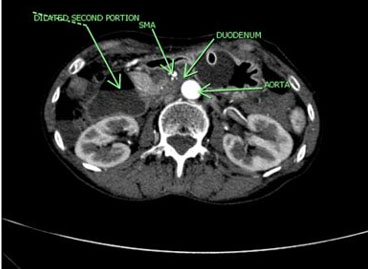

The patient presented intense epigastric pain, vomiting, and constipation, requiring hospitalization. Symptoms subsided when lowering enteral nutrition infusions up to 20 cc/h, and exacerbated when enteral nutrition volume was increased. The physical exam showed a normal abdomen, no distension, soft, with slight sensitivity at the epigastrium and no signs of peritoneal irritation. By this time, the patient’s weight was 36 kg, reaching a body mass index (BMI) of 16.8 kg/m2. An upper digestive endoscopy showed an esophageal stricture with actinic appearance, requiring endoscopic dilation. However, since stenosis does not explain the feeding intolerance, a CT scan was performed. It reported a significant decrease in intra-abdominal fat, especially in the retroperitoneal fat panniculus, associated with a change in caliber and dilation of the second and third portion of the duodenum (Figure 1 and Figure 2), possibly due to partial compression of the third portion between the aorta and the SMA. No other signs of intestinal obstruction were observed. Superior mesenteric artery syndrome was suspected so the images were reviewed with the radiologist, finding an aorto-mesenteric angle of 17° (Figure 3) and an aorto-mesenteric distance of 7.3 mm (Figure 4).

Figure 2: Dilated second portion of the duodenum and constricted duodenum between SMA and aorta in patient no. 1, transverse view.